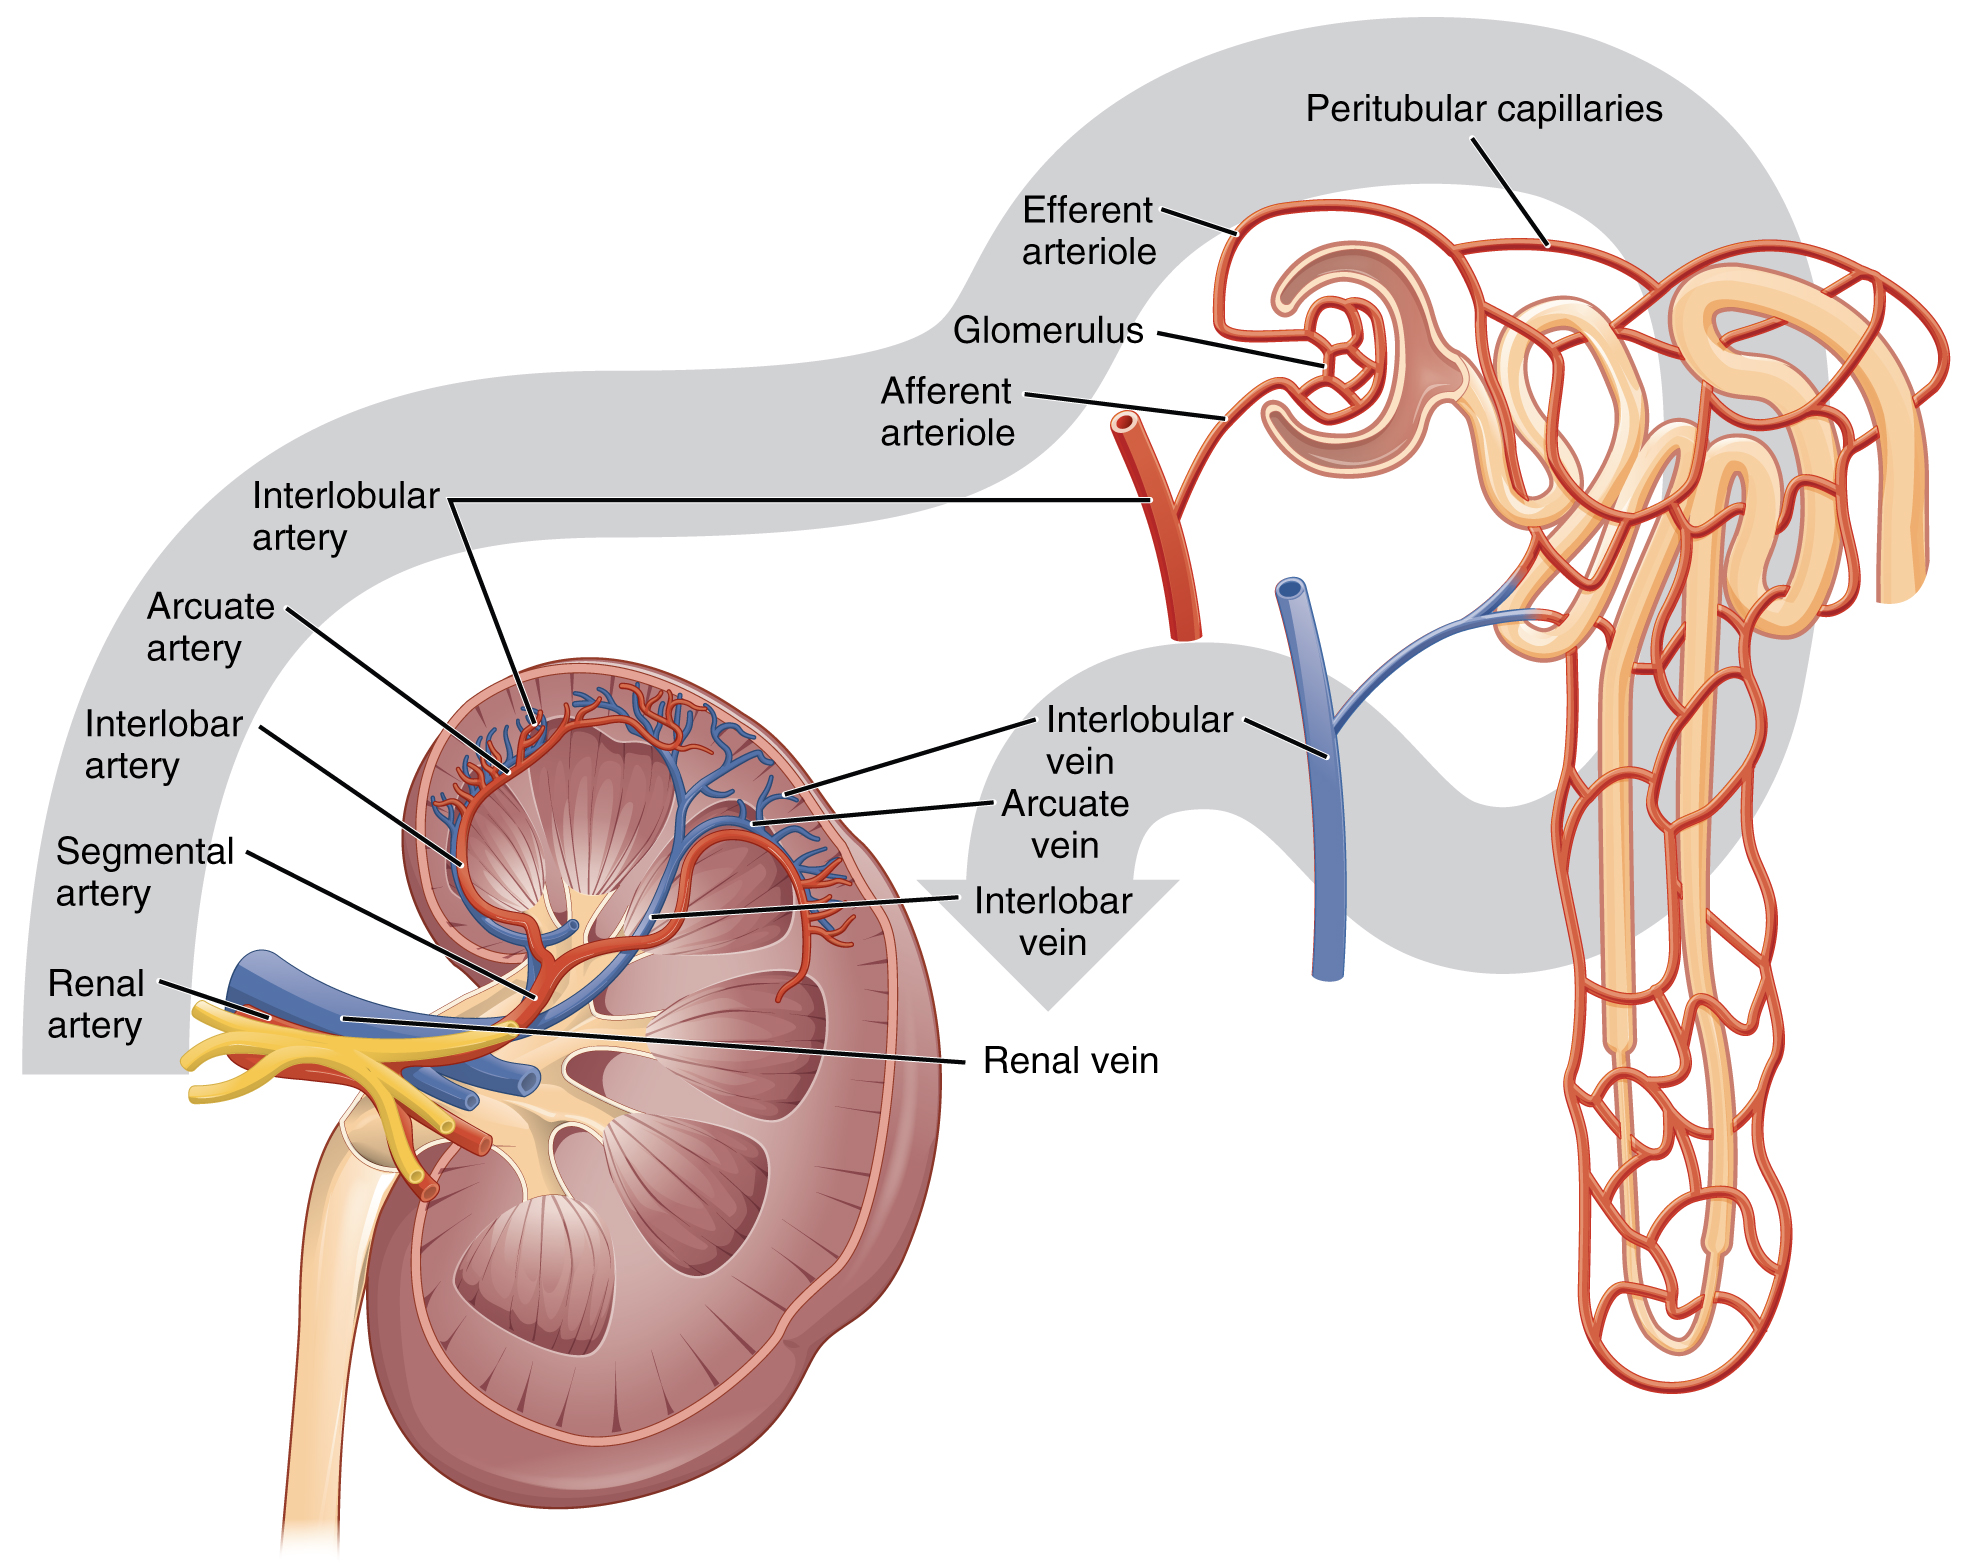

The kidneys monitor and regulate the levels of hydrogen ions h and bicarbonate ions in the blood to control blood ph. Glomerular filtration glomerular filtration is the renal process whereby fluid in the blood is filtered across the capillaries of the glomerulus. The right kidney is lower than the left due to displacement by the liver.

25 2 Microscopic Anatomy Of The Kidney Anatomy Of The

25 2 Microscopic Anatomy Of The Kidney Anatomy Of The

Principles Of Anatomy And Physiology Kidney Renal Artery

Principles Of Anatomy And Physiology Kidney Renal Artery